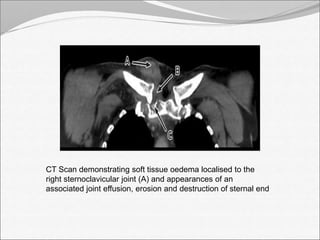

CT Scan demonstrating soft tissue oedema localised to the

right sternoclavicular joint (A) and appearances of an

associated joint effusion, erosion and destruction of sternal end

CT Scan demonstratingsoft tissue oedema localised to the right sternoclavicular joint (A) and appearances of an associated joint effusion, erosion and destruction of sternal end